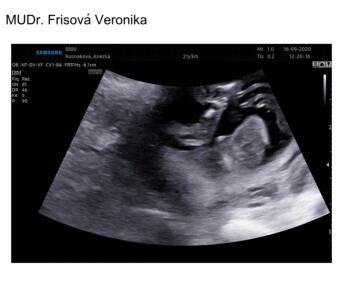

Krásný dobrý den v 18+6 jsem byla na ultrazvuku. Dostala jsem tyto fotky jsou zaměřené přímo na genitálie. Nyní už jsem 32+0 rada bych věděla co čekám za miminka přeji hezký den. Anežka. R

Dobrý den, bohužel fotografie jsou z jiného úhlu, než je ideální pro určování pohlaví. Neváhejte se zeptat Vašeho gynekologa, co na ultrazvuku vidí. Avšak ve 3. trimestru nemusí být snadné pohlaví vizualizovat. Hezký den